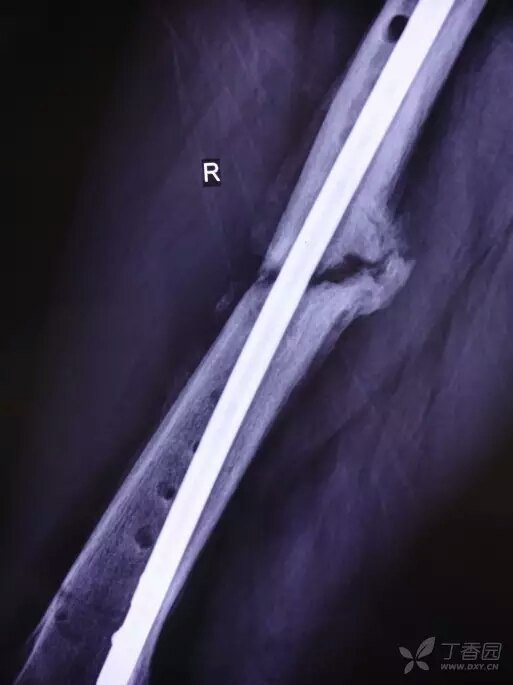

骨不連是骨折術(shù)后常見并發(fā)癥,又稱為骨折不愈合,是骨折端在某些條件影響下,骨折愈合功能停止,甚至骨折端形成假關(guān)節(jié)。在所有骨折病人中,大約 5% 的患者愈合困難。 根據(jù) FDA 1986 年的定義,一定部位和類型的骨折未能在其平均時(shí)間內(nèi)愈合(通常 3~6 月)稱為延遲愈合(delayedunion);損傷和骨折至少 9 個(gè)月,并且沒有進(jìn)一步愈合傾向已經(jīng)有 3 個(gè)月稱為骨不連接。 常見原因 1. 全身因素:年齡、全身營(yíng)養(yǎng)狀況、糖尿病、庫(kù)欣綜合征、甲狀腺功能減退、非類固醇類抗炎藥、化療、吸煙等; 2. 局部因素:血液供應(yīng)、機(jī)械力學(xué)穩(wěn)定、骨折斷端分離移位、軟組織坎頓、感染; 3. 其他:另外,開放性骨折、多節(jié)段骨折、粉碎性骨折、固定不牢固、固定時(shí)間不夠、不恰當(dāng)?shù)那虚_復(fù)位、骨折端分離、放射性骨折等也容易發(fā)生骨不連;骨折合并主要軟組織破壞(如開放骨折); 高能量損傷機(jī)制導(dǎo)致的骨折(如交通事故或高處墜落傷); 老年人或免疫功能低下的人; 同時(shí)合并有代謝性骨骼疾病患者的骨折。 分類 根據(jù)骨折端活力情況,分為 2 種類型: 1. 第一種為血管豐富肥大型(圖 1)。 骨折端富有生命力,產(chǎn)生明顯的生物學(xué)效應(yīng)。該種類型又可以分為幾種亞型: (1)象足型骨不連 ?骨折端有肥大而豐富的骨痂,常因?yàn)榛顒?dòng)過(guò)度引起骨不連; (2)馬蹄型骨不連 ?輕度肥大骨痂少,常因?yàn)楣潭ú焕喂桃鸸遣贿B; (3)營(yíng)養(yǎng)不良型骨不連 ?骨折端無(wú)肥大及骨痂,常常因骨折對(duì)位不良引起。 圖 1 為肥大型骨不連 2. 第二種骨不連為缺血萎縮型(圖 2) 骨折端缺乏活力,生物學(xué)反應(yīng)少。分為扭轉(zhuǎn)楔形骨不連、粉碎性骨不連、缺損型骨不連、萎縮型骨不連。 圖 2 為萎縮型骨不連 診斷 骨折端有異常活動(dòng),伴有局部疼痛、壓痛及傳導(dǎo)叩痛。 X 線片:顯示骨折端互相分離,間隙較大,骨端硬化,萎縮疏松,髓腔封閉。 治療 骨折延遲愈合可以考慮非手術(shù)治療 1~3 月,仍然未愈合建議手術(shù)治療。 1. 非手術(shù)治療 包括輔助外固定、高能震波、電磁波刺激、沖擊波治療等; 2. 手術(shù)治療 骨不連的手術(shù)治療計(jì)劃應(yīng)包括改善局部生物學(xué)行為和加強(qiáng)其機(jī)械穩(wěn)定性。 常用的改善局部生物性狀的治療方法包括:去除感染灶,骨移植,骨髓移植和應(yīng)用 Ilizarov 方法。 提高機(jī)械穩(wěn)定性的方法包括:鋼板螺釘內(nèi)固定術(shù),髓內(nèi)釘內(nèi)固定和外固定架。 臨床上對(duì)于骨不連的治療,骨移植加恢復(fù)骨折端力學(xué)穩(wěn)定性仍是主流,主要包括以下幾種方法: 1. 去皮質(zhì)術(shù)聯(lián)合骨移植 是刺激肥大型和萎縮型骨不連生長(zhǎng)最有效的生物學(xué)手段,術(shù)后有望形成一個(gè)肥大的橋接性骨痂,這是治療骨不連的一個(gè)標(biāo)準(zhǔn)程序。 2. 自體骨移植 自體骨移植特別是松質(zhì)骨移植的適應(yīng)證特別廣泛,著重點(diǎn)是在萎縮型骨不連的治療,它通過(guò)增強(qiáng)生物學(xué)反應(yīng)對(duì)骨質(zhì)愈合產(chǎn)生強(qiáng)烈刺激。并且骨移植能夠填充或橋接骨缺損。但在感染環(huán)境中,由于自體松質(zhì)骨具有血運(yùn)快速重建的能力,可以抵抗感染帶來(lái)的破壞作用,從而成為感染時(shí)唯一可選的材料。 常用的植骨方法 ①游離植骨。是一種常規(guī)的植骨方法,對(duì)小的骨缺損,采用帶皮質(zhì)的松質(zhì)骨植?入,能起到填充和支撐作用。骨缺損行脛腓骨融合時(shí),除在脛腓骨間植骨外,應(yīng)同時(shí)在缺損處植骨。 ②帶血管蒂骨移植。為移植提供了良好的血液循環(huán),有利于愈合。 總之,骨不連治療方法較多,主要注重的個(gè)性化治療,根據(jù)病人情況選擇治療不同治療方法。 預(yù)防 防止骨折不愈合最重要的一件事情就是避免吸煙。其他因素包括良好的營(yíng)養(yǎng)、堅(jiān)持實(shí)施醫(yī)生推薦的康復(fù)計(jì)劃、定期復(fù)查。